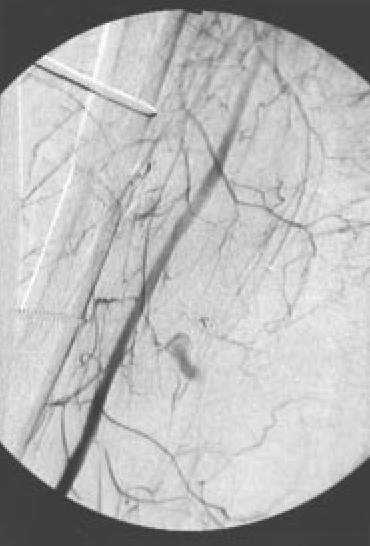

| Fig. 7B.: Imagen obtenida en arteriografía, mostrando "stop" a nivel de arteria femoral |